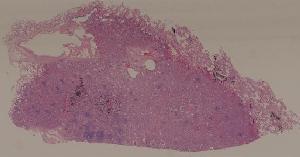

69. Hepatocellular carcinoma